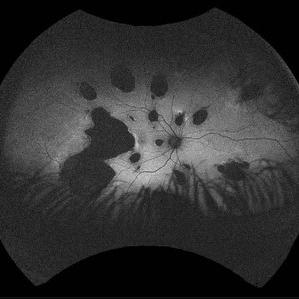

Idiopathic multifocal choroiditis (IMFC) FAF

23 -year- old man with gradually decreased vision specially in right eye, multiple lesions are in the retinal and choroidal tissue. IMCP causes episodes of inflammation that can occur bilaterally, simultaneously or separately

Photographer: Mohammadkarim Johari, Shiraz university of medical science

Condition/keywords: inflammatory choroidopathy, multifocal chorioretinitis (MCP), multifocal choroiditis